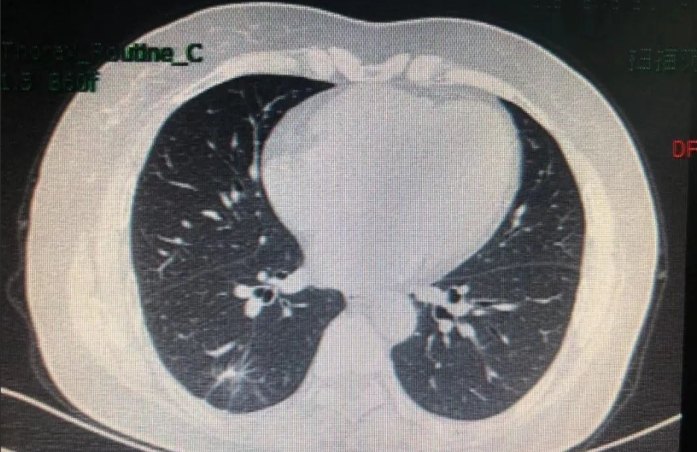

作为一名经常为患者解读肺部影像报告的胸腔科医师,我很理解大家对「肺結節」的担忧。网络上关于「肺結節傳染」的说法更是让许多人感到恐慌。今天,我希望能用一篇详尽的文章,以专业但口语化的方式,跟大家好好聊聊肺結節,特别是厘清「肺結節傳染」的迷思,并深入探讨大家关心的各个方面,包括肺結節原因、肺部結節症狀、大家常问的肺部結節會痛嗎、关键的肺結節怎麼治療,以及特定位置的右下肺結節原因。

当我们在CT或X光片上看到一个肺結節,最重要的第一步就是尝试弄清楚它的肺結節原因。这就像是侦探破案,需要根据结节的形态、大小、位置、你的病史和症状(如果有的话)来综合判断。关于肺結節傳染的担忧,往往源于对某些特定原因的误解。